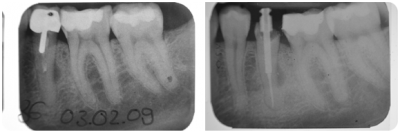

Bild 1: alte insuffiziente Wurzelfüllung mit seitlicher Entzündung; Bild 2: neue Wurzelfüllung mit Titanschraube;

Endodontie ist die Lehre von der Behandlung des Wurzelkanalsystems.

In früheren Zeiten hat man um jeden Preis versucht, Zähne durch Wurzelbehandlungen zu erhalten. Da bei jeder Wurzelbehandlung aber nur der gerade Kanal aufbereitet werden kann und sich im letzten Wurzeldrittel immer Seitenkanäle befinden, die nicht versäubert werden können, ist auch die beste lege artts Wurzelbehandlung kein Garant für ein dauerhaftes Ruhigbleiben des Zahnes.

Durch moderne Techniken wie die elektronische Längenbestimmung und die maschinelle Aufbereitung kann aber die Erfolgsrate deutlich gesteigert werden. In unserer Praxis werden diese Zähne meist mit Kunststofffüllungen versorgt und eine teure Überkronung vermieden